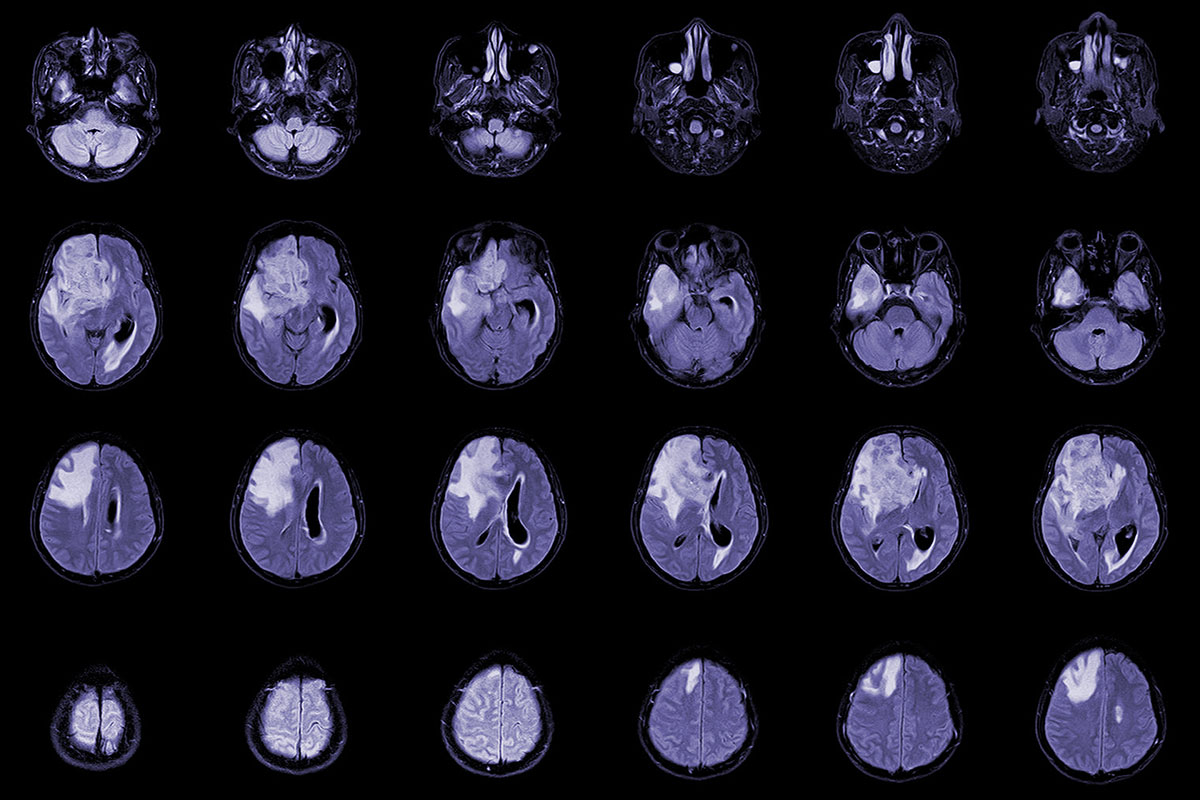

Patients with brain cancer may benefit from treatment to boost white blood cells

Blocking immune suppressor cells in mice with glioblastoma improved survival